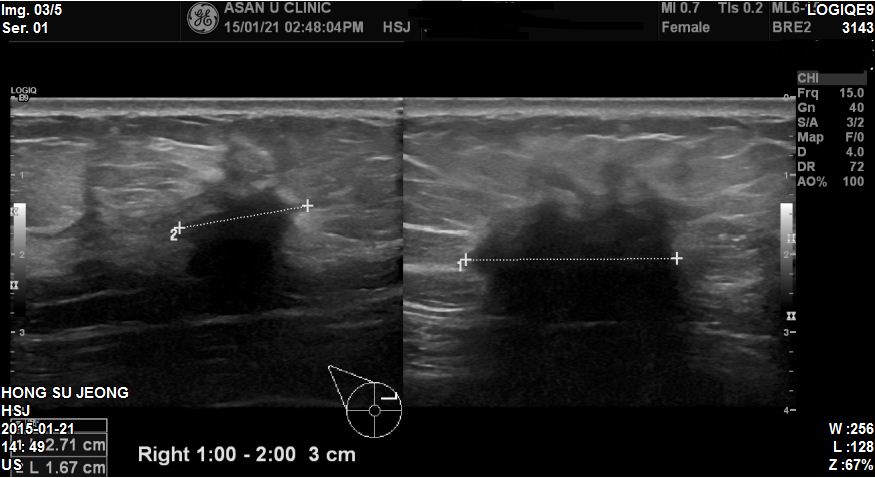

건진상 이상소견으로 내원하신 53세 환자분이십니다.

본원에서 우측 상내측에 2.7cm혹 조직검사 시행하였고

겨드랑이에 임파절이 부어있어 세침검사 시행하였습니다

결과 침윤성유방암진단되었고 겨드랑이까지 전이되어있었습니다.